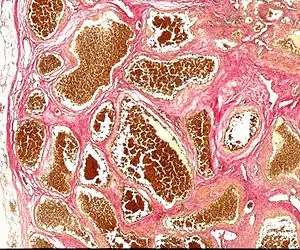

| Histology of a cavernous hemangioma | |

Cerebral cavernous malformation (CCM) is a cavernous hemangioma that arises in the central nervous system. It can be considered to be a variant of hemangioma, and is characterized by grossly large dilated blood vessels and large vascular channels, less well circumscribed, and more involved with deep structures, with a single layer of endothelium and an absence of neuronal tissue within the lesions. These thinly walled vessels resemble sinusoidal cavities filled with stagnant blood. Blood vessels in patients with cerebral cavernous malformations (CCM) can range from a few millimeters to several centimeters in diameter. Most lesions occur in the brain, but any organ may be involved.[1]